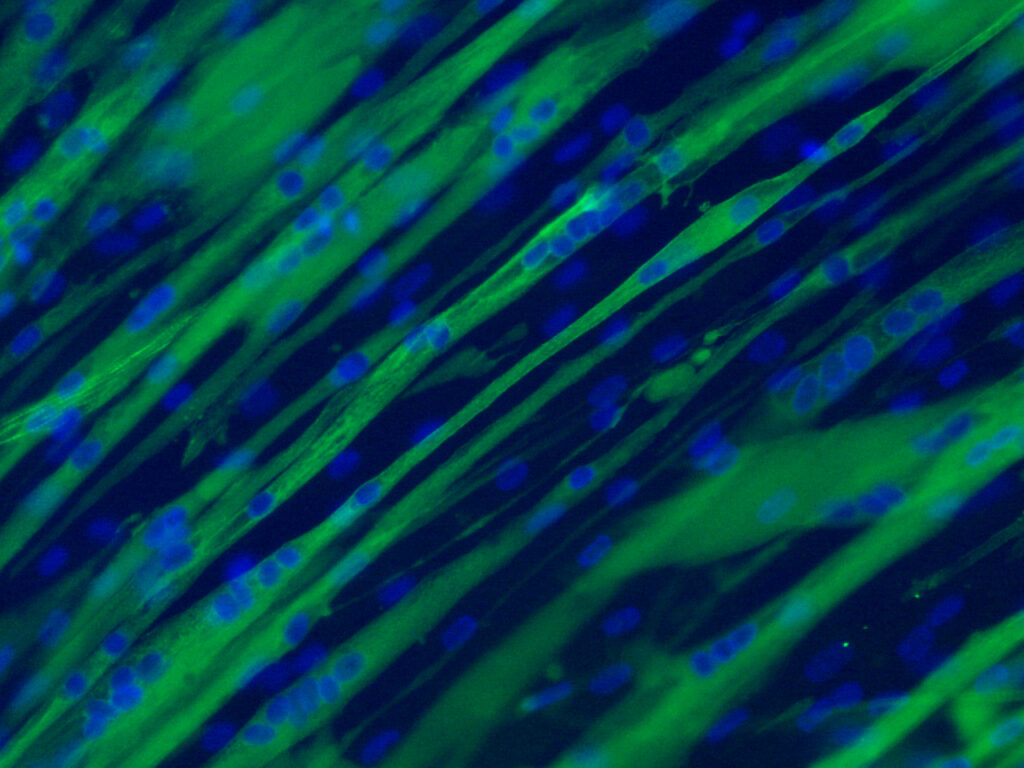

Plataforma de Cultivos Celulares

La Plataforma de cultivos celulares (PCC) incluye tres salas de cultivo celular: dos salas están dedicadas al cultivo de líneas celulares primarias y establecidas, y la tercera sala se utiliza para infectar células con virus bajo el nivel de bioseguridad 2. La plataforma está actualmente activa en tres áreas: (i) Investigación: la PCC es responsable…